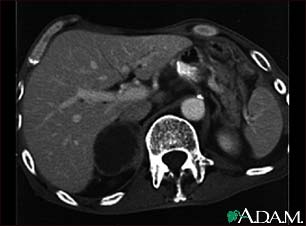

Adrenal metastases, CT scan

This CT scan of the upper abdomen shows an adrenal metastasis (spreading of a tumor to the adrenal gland, above the kidney) in a person with lung cancer.